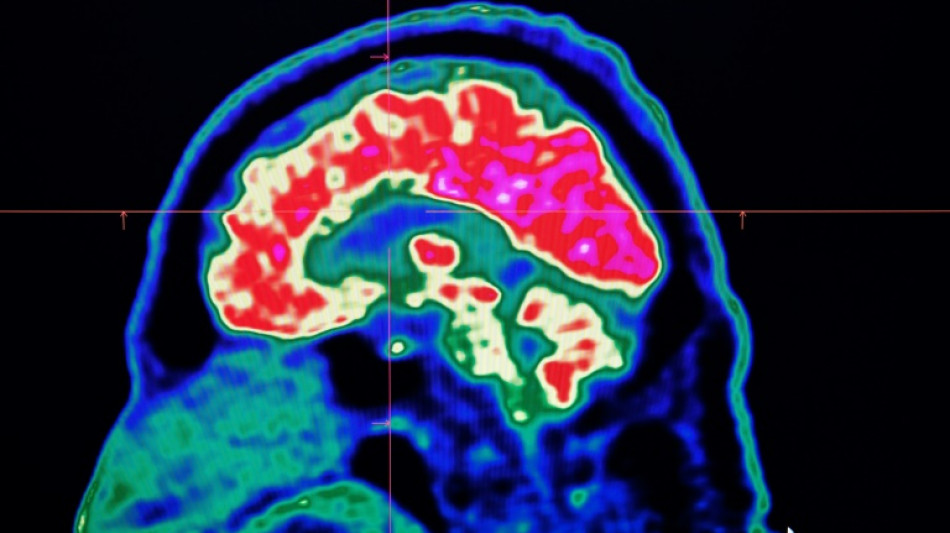

What are all these microplastics doing to our brains?

Tiny shards of plastic called microplastics have been detected accumulating in human brains, but there is not yet enough evidence to say whether this is doing us harm, experts have said.

These mostly invisible pieces of plastic have been found everywhere from the top of mountains to the bottom of oceans, in the air we breathe and the food we eat. They have also been discovered riddled throughout human bodies, inside lungs, hearts, placentas and even crossing the blood-brain barrier.

The most prominent study looking at microplastics in brains was published in the journal Nature Medicine in February.

The scientists tested brain tissue from 28 people who died in 2016 and 24 who died last year in the US state of New Mexico, finding that the amount of microplastics in the samples increased over time.

The study made headlines around the world when the lead researcher, US toxicologist Matthew Campen, told the media that they detected the equivalent of a plastic spoon's worth of microplastics in the brains.

Campen also told Nature that he estimated the researchers could isolate around 10 grammes of plastic from a donated human brain -- comparing that amount to an unused crayon.